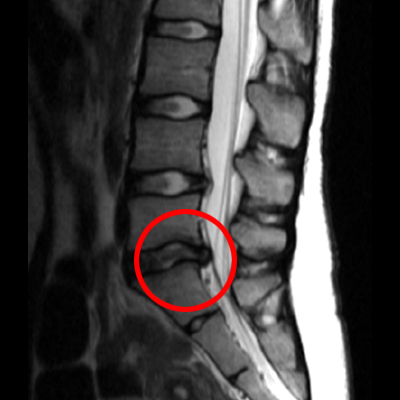

12월 경 mri 찍었을 때

목 디스크 소견이 보인다고 하였으나

디스크 진단은 안내려줌

건강검진 할 시즌이어서 목 mri 찍어봤는데

디스크 진단이 나왔더라구요